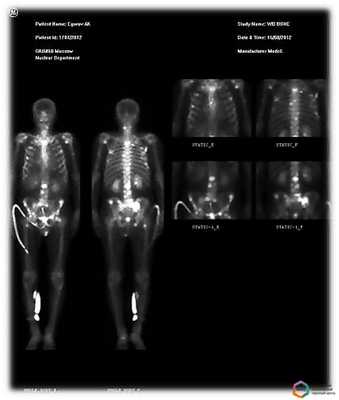

- Планарная сцинтиграфия - наиболее простая методика. Позволяет получать двухмерные снимки, как во время рентгенографии, на которых видно распределение радиофармпрепарата. Этот вид исследования часто используют, чтобы обнаружить в костях первичную злокачественную опухоль или метастазы.

- Однофотонная эмиссионная компьютерная томография (ОФЭКТ) позволяет получить серию смежных двухмерных изображений, на которых также визуализируется распределение радиоактивного индикатора.

- ОФЭКТ-КТ - наиболее информативная методика. Во время исследования данные сцинтиграфии совмещают со снимками, полученными с помощью КТ. Это позволяет получать трехмерные изображения, судить не только о патологических изменениях в костях, но и о точной локализации очагов.

Повышение накопления различных препаратов на основе фосфата в области КПС при сакроилеитах продемонстрировано в ряде исследований [2, 11]. Так, в исследовании Ian M. было показано, что повышенное накопление РФП в КПС может предшествовать появлению рентгенологических признаков сакроилеита у пациентов с определенным анкилозирующим спондилитом. Кроме того, метод позволяет выявить сакроилеит у пациентов с другими формами заболеваний суставов и позвоночника [11]. В исследовании Rothwell R.S. et al. количественная сцинтиграфия КПС позволила выявить признаки сакроилеита у 40% женщин с хроническими болями в нижней части спины. При этом показано, что в большинстве случаев эти сакроилеиты регрессировали со временем [12]. Усовершенствованная радионуклидная методика ОФЭКТ/КТ позволяет дополнительно улучшить эффективность и точность выявления сакроилеита у пациентов со спондилоартритами. Значительным преимуществом сцинтиграфии является способность с высокой специфичностью и чувствительностью выявлять целый ряд поражений позвоночника, которые, как правило, приходится дифференцировать в реальной практике при болях в спине. К таким заболеваниям и состояниям можно отнести костные метастазы (чувствительность - 74-97%, специфичность - 64-93%), спондилиты (чувствительность - 90%, специфичность - 78%); анкилозирующий спондилит (чувствительность - 26-45%, специфичность - 100%) [13]. Кроме того, с высокой точностью могут диагностироваться дисциты [14], компрессионные переломы позвонков [14]. Таким образом, сцинтиграфические методы (планарная сцинтиграфия, ОФЭКТ, ОФЭКТ/КТ) могут использоваться при дифференциальной диагностике болей в спине, особенно боли воспалительного типа, а также при подозрении на сакроилеит, анкилозирующий спондилит, инфекционные спондилиты.